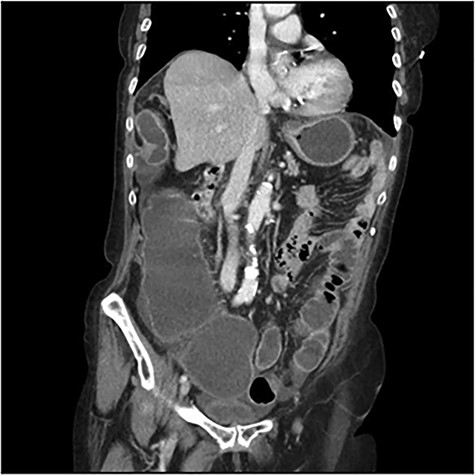

The scanner demonstrated a colonic occlusion resulting from an incarceration, which was diagnosed as a hernia of Bochdalek containing the hepatic angle of the colon (Fig. 2–4).

CT scan images demonstrating a right diaphragmatic hernia containing intestine.